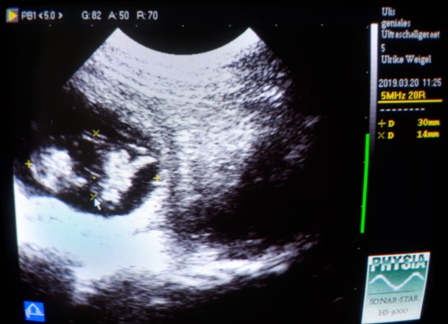

20.03.2019 - 34. Tag der Trächtigkeit

Ich weiß genau wie groß unsere Kindlys heute sind :)

Da ich das Ultraschallgerät bis zur Geburt mal wieder von unserem Wohnzimmertisch ;)

entfernen wollte(..es ist mega schwer!!), dachte ich... so gaaanz kurz kann ich doch noch mal reingucken :)

Phoebe legt sich schon alleine in unser großes Kuschelhundebett und streckt mir den Bauch entgegen ;)

.. sie sind 3 cm lang und ca. 1,4 cm breit, das passt genau in die Zeit, glaube ich!

Ich lese mich so nach und nach durch das riesige Buch, welches dem Gerät beilag.

Und langsam kann ich die Feinheiten etwas besser nutzen :)

Sechs Kindlys konnte ich heute entdecken, alle mit schlagenden Herzchen, der Rest war undurchdringlich.

Phoebe hat ein sehr dichtes Fell und hatte gut gegessen. Also weiter alles offen!!